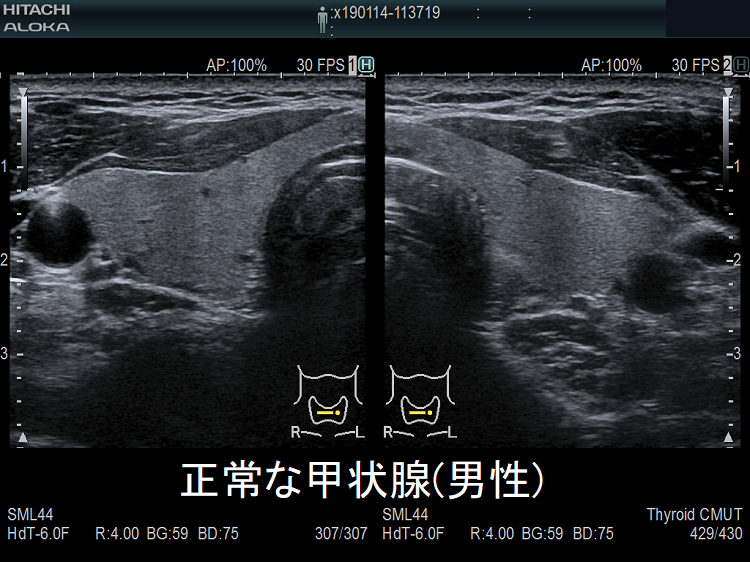

「正常な甲状腺」と診断するには、どうすればよいか?そもそも、「正常な甲状腺」とはどのような甲状腺を指すのでしょうか?「異常のあるもの」を「異常」と言うのは簡単な事ですが、「異常が無い」と断言するのは意外と難しい事があります。

JABTS(日本乳腺甲状腺超音波医学会)の定義では、

- 甲状腺の病気がなく、

- (採血で)甲状腺ホルモンの値が正常

- 超音波検査で異常が認められない

ものが「正常な甲状腺」です。すなはち、甲状腺エコー(甲状腺超音波検査)しなければ、「正常な甲状腺」と診断できない事になります。1. 2.は簡単ですが、3.は甲状腺エコー(甲状腺超音波検査)に精通した専門医の技術が必要になります。

甲状腺の基本を長崎甲状腺クリニック(大阪)院長が解説。正常な男性の甲状腺は女性の約1.5倍の大きさで、女性と比べてかなり下方にある。甲状腺ホルモンは体の新陳代謝を活発にするホルモン。甲状腺濾胞で巨大蛋白サイログロブリンにチロシンやヨードが結合し甲状腺ホルモン(T3,T4)が合成される。血液中の甲状腺ホルモン(FT4,FT3)が多くなると視床下部―下垂体が感知し、下垂体からの甲状腺刺激ホルモン(TSH)の分泌が低下。このネガティブフィードバック機構で甲状腺ホルモンの血中濃度は一定に保たれる。甲状腺ホルモンは季節変動、年齢による変化あり。